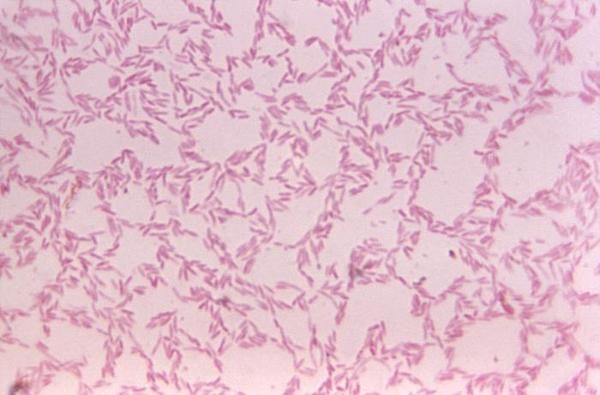

腸道細菌影響免疫系統健康

人體是數以兆計細菌的家,比我們自己的細胞數量還多10倍。腸道裡的細菌通常是有益的,可以幫助我們消化,以及生成維生素 B 與 K ,不過研究也顯示腸道細菌用不同的方式協助著免疫系統。例如,益菌會把壞菌約束在上皮或黏膜組織,以免它們做怪;益菌也會協助免疫系統分辨誰是敵誰是友,及一些無害的抗原,它們會協助抑止過敏反應。

益菌同時也可能影響免疫系統對抗原的敏銳度,降低自體免疫疾病發生的機率。益菌也會協助製造一些有用的抗體,並影響一些腸道蛋白質的表現,讓免疫系統更有效地在腸道中運作。

▲腸道細菌。((Photo Credit: CDC))